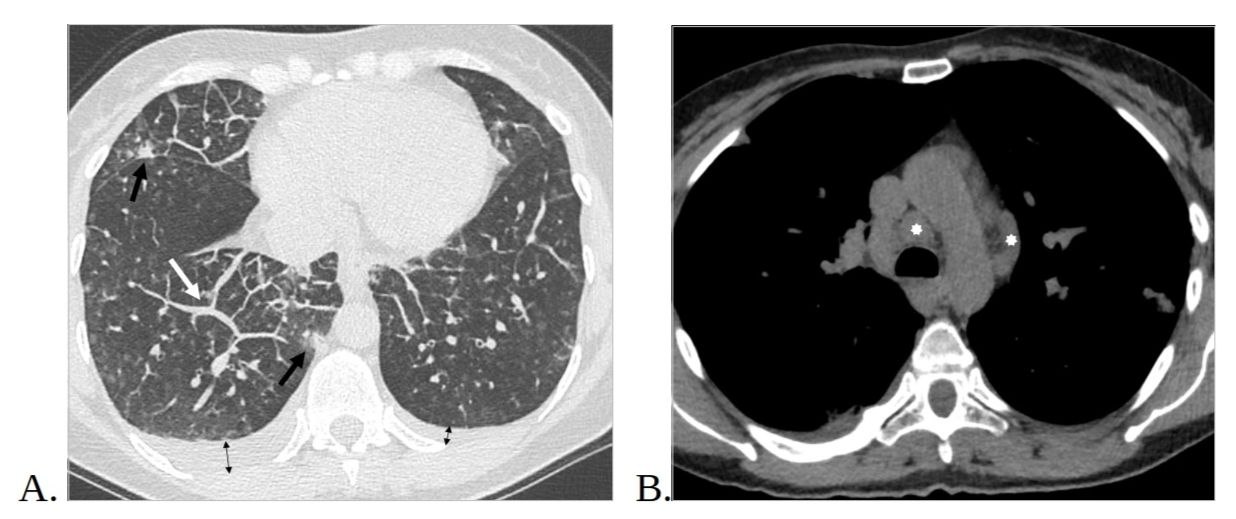

2. Рис.2 МСКТ органов грудной клетки, аксиальная проекция. | |

4. Рис.4. МСКТ органов грудной клетки, аксиальные срезы. | |